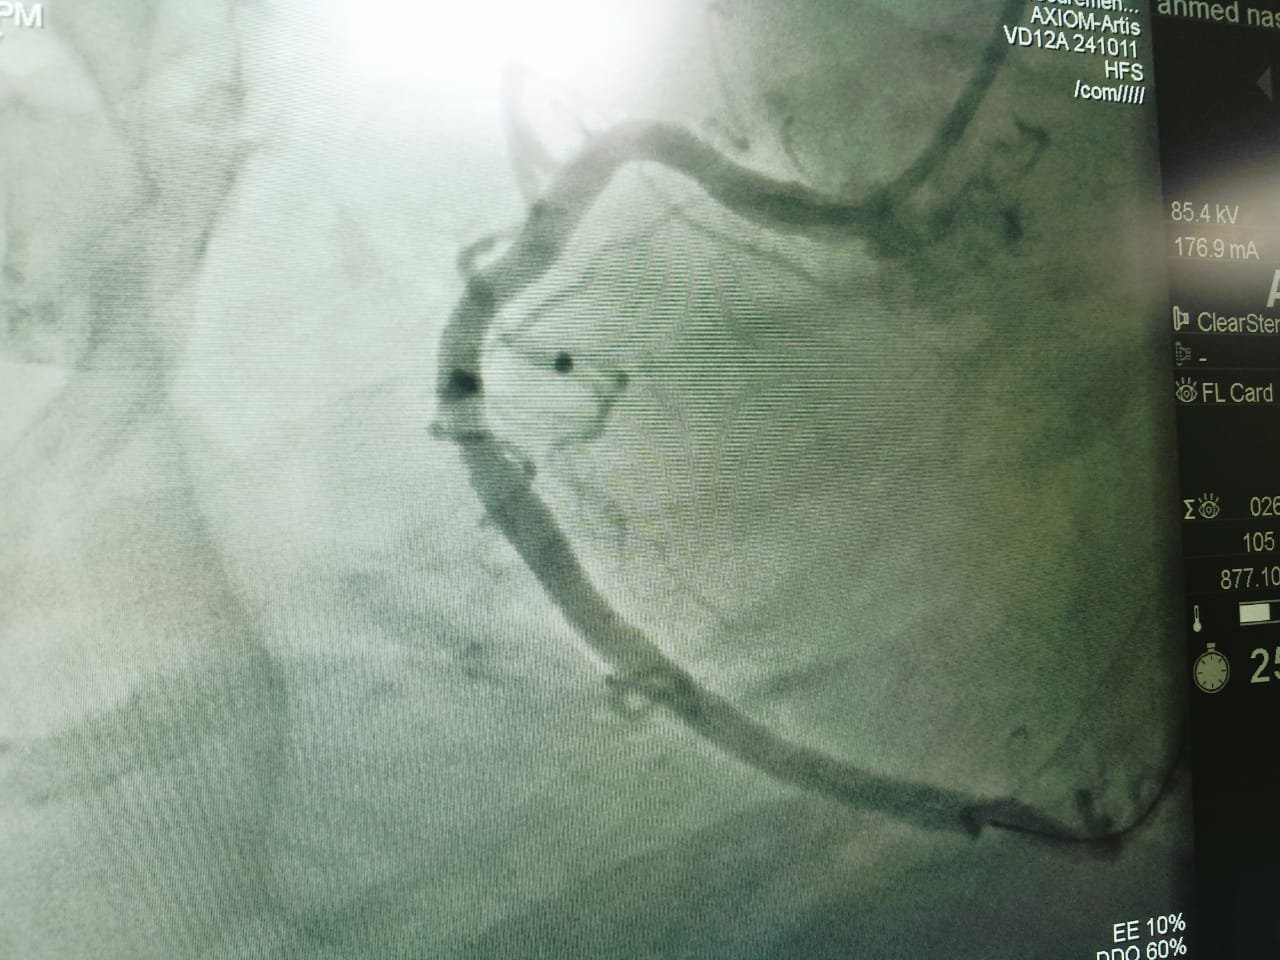

وأشار الأستاذ محمود عبدالفتاح مدير الإعلام والعلاقات العامة بالمديرية، إلى أن حالات القسطرة القلبية المائة التي تم إجراؤها بمستشفى فاقوس المركزي منذ تشغيل الوحدة في ٢٤ فبراير الماضي، تنوعت ما بين ٥٩ حالة قسطرة تشخيصية، و٤١ حالة قسطرة علاجية والتي تضمنت تركيب دعامات وتوسيع الشرايين باستخدام البالون، وتم خلالها إنقاذ حياة العديد من الحالات الطارئة الحرجة، وتم خروج جميع المرضى بفضل الله بحالة جيدة، بعد تقديم الرعاية الطبية اللازمة لهم قبل وبعد إجراء القسطرة القلبية بالمستشفى.